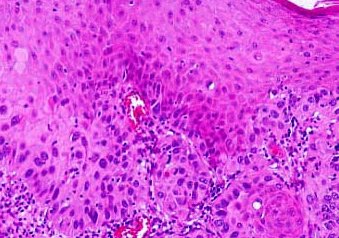

A repeated biopsy revealed a histology similar to the above picture.

What is the diagnosis?